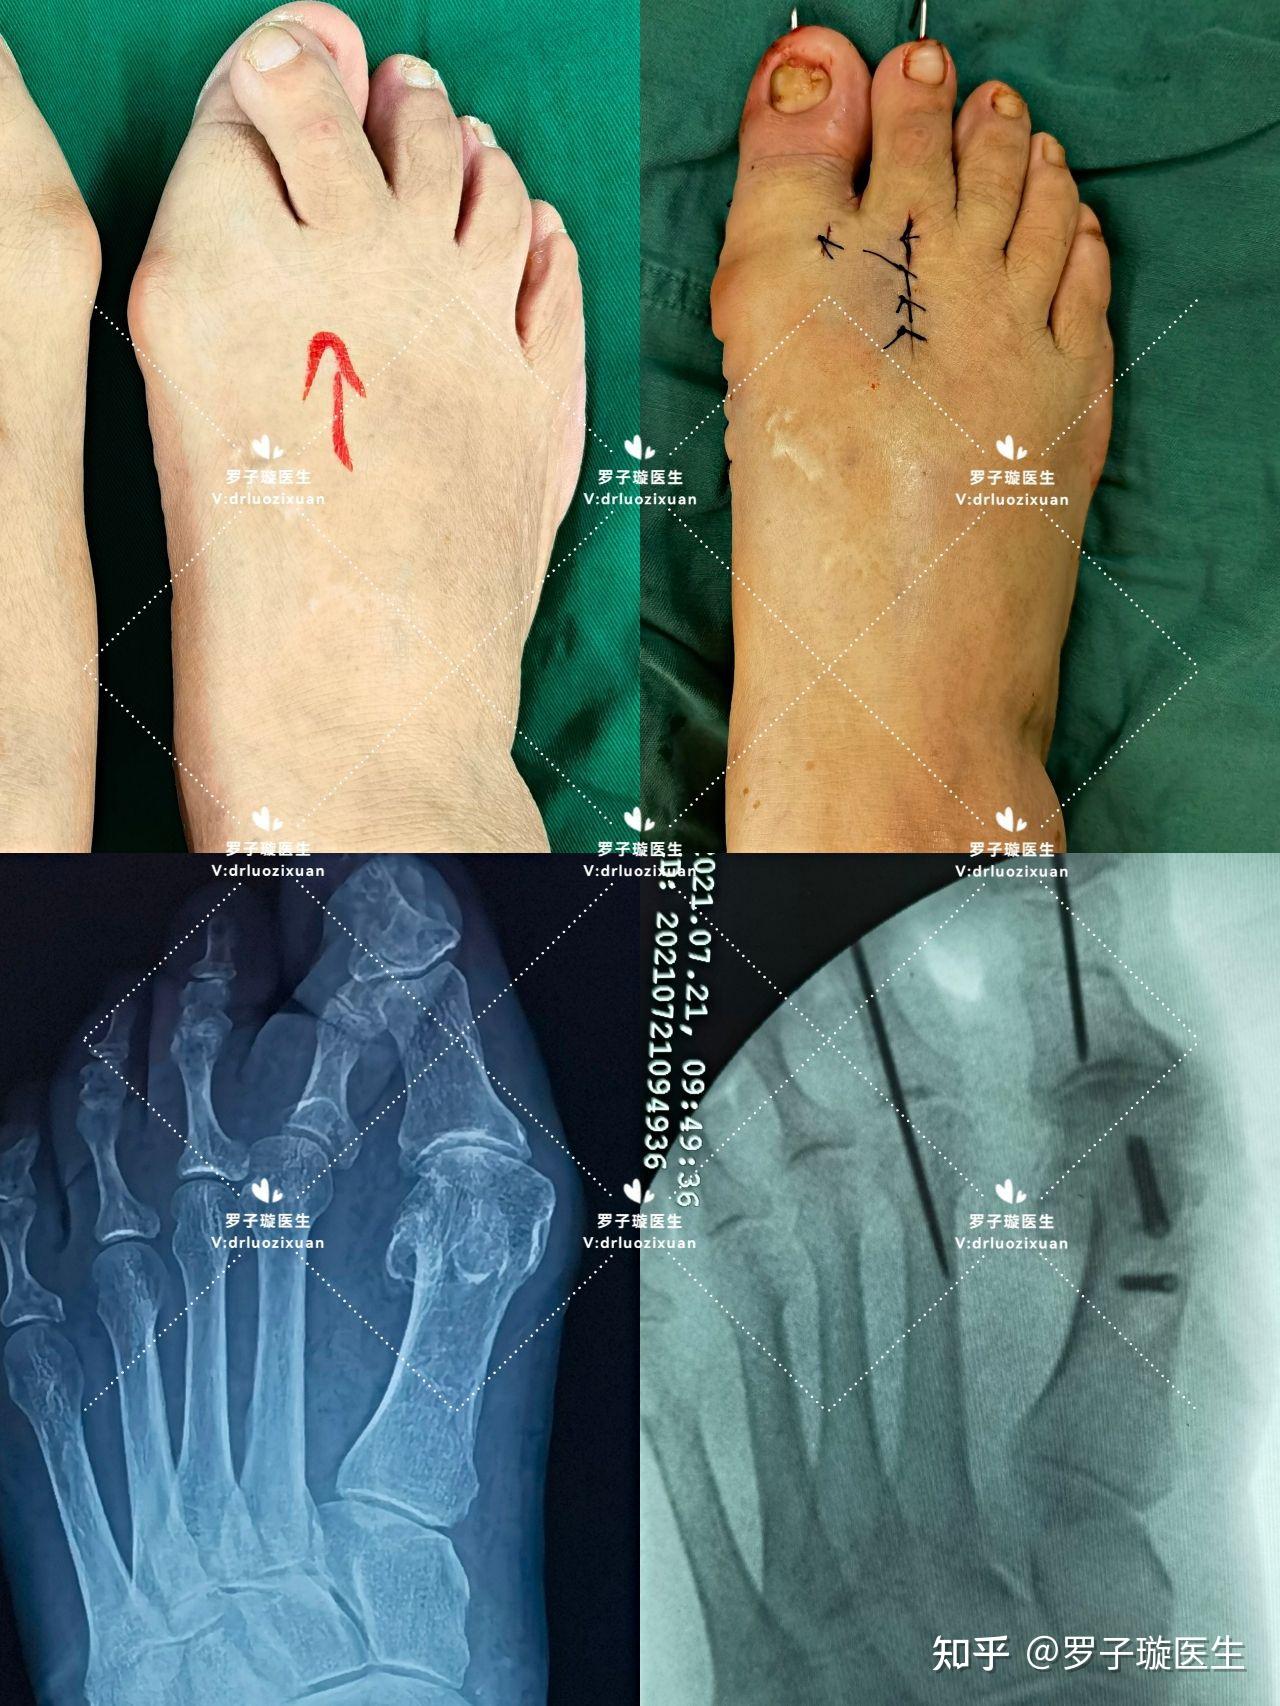

踇外翻叠趾畸形 术前术后 对照图

hva>35度,ima>16度,跖趾关节脱位已经属于叠趾畸形,属于重度范围.